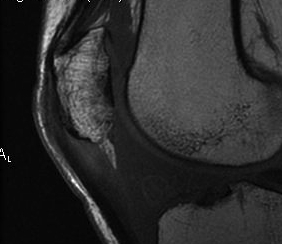

MRI

Cyst / Degeneration

Traction spurs / calcification / ossicles